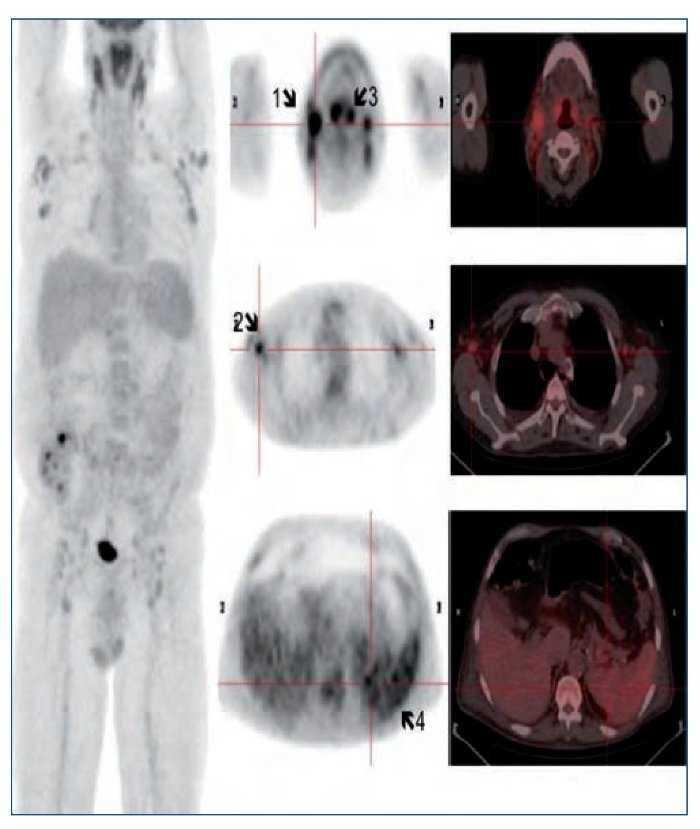

Se instaura tratamiento con sueroterapia, reposición de seroalbúmina y suplementos nutricionales. Por la presencia de síndrome tóxico y adenopatías generalizadas, y con la sospecha diagnóstica de síndrome linfoproliferativo, se decide solicitar como prueba diagnóstica una PET/TC con 18F-FDG (figura 1).

Figura 1. Flechas 1 y 2: Adenopatías hipermetabólicas laterocervicales y axilares, respectivamente. Flecha 3: Engrosamiento amigdalar hipermetabólico. Flecha 4: Hipermetabolismo difuso esplénico.

La PET/TC con 18F-FDG muestra imágenes de cuerpo entero que identifican múltiples adenopatías discretamente hipermetabólicas laterocervicales (la de mayor tamaño de 23 mm y SUVmáx 5,5 g/ml), axilares (18 mm, SUVmáx 4 g/ml) (figura 1, flechas 1 y 2), cadenas ilíacas externas e inguinales (16 mm, SUVmáx 3 g/ml). Se observa también un marcado engrosamiento hipermetabólico amigdalar bilateral y simétrico (figura 1, flecha 3) y aumento difuso de la captación de la FDG a nivel esplénico (sin alteraciones morfológicas) con respecto a la captación hepática (figura 1, flecha 4). A estos hallazgos se asocia un discreto derrame pleural bilateral sin captación patológica que condiciona un colapso pasivo de lóbulos inferiores sin clara evidencia de lesiones pleurales o pulmonares. El tamaño amigdalar, las numerosas adenopatías de características discretamente hipermetabólicas y el aumento difuso de la captación esplénica plantean el diagnóstico diferencial entre un proceso inflamatorio-reactivo/infeccioso-sistémico (infecciones por herpes virus, virus de Epstein-Barr [VEB], citomegalovirus, virus de la inmunodeficiencia humana, micobacterias, enfermedades granulomatosas, entre otras) frente a un proceso linfoproliferativo. Ante dichos hallazgos se solicitan pruebas dirigidas a la identificación de virus del herpes, VEB, citomegalovirus, virus de la inmunodeficiencia humana, micobacterias y antígenos tumorales. Entre ellas destacamos VEB IgG: 25,1 UI/ml, IgM negativo. Reacción en cadena de la polimerasa (PCR) para VEB: 4.974 copias. El resto de pruebas fueron negativas. Se realiza biopsia ganglionar cervical derecha y amidgalectomía por parte del servicio de otorrinolaringología (figura 2).